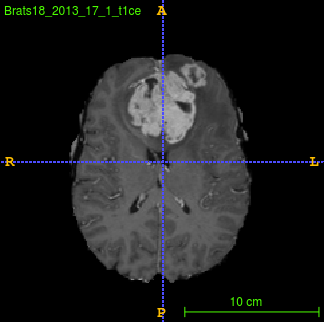

Segmentation of brain tumor from magnetic resonance imaging (MRI) is a vital process to improve diagnosis, treatment planning and to study the difference between subjects with tumor and healthy subjects. In this paper, we exploit a convolutional neural network (CNN) with hypercolumn technique to segment tumor from healthy brain tissue. Hypercolumn is the concatenation of a set of vectors which form by extracting convolutional features from multiple layers. Proposed model integrates batch normalization (BN) approach with hypercolumn. BN layers help to alleviate the internal covariate shift during stochastic gradient descent (SGD) training by zero-mean and unit variance of each mini-batch. Survival Prediction is done by first extracting features(Geometric, Fractal, and Histogram) from the segmented brain tumor data. Then, the number of days of overall survival is predicted by implementing regression on the extracted features using an artificial neural network (ANN). Our model achieves a mean dice score of 89.78%, 82.53% and 76.54% for the whole tumor, tumor core and enhancing tumor respectively in segmentation task and 67.90% in overall survival prediction task with the validation set of BraTS 2018 challenge. It obtains a mean dice accuracy of 87.315%, 77.04% and 70.22% for the whole tumor, tumor core and enhancing tumor respectively in the segmentation task and a 46.80% in overall survival prediction task in the BraTS 2018 test data set.